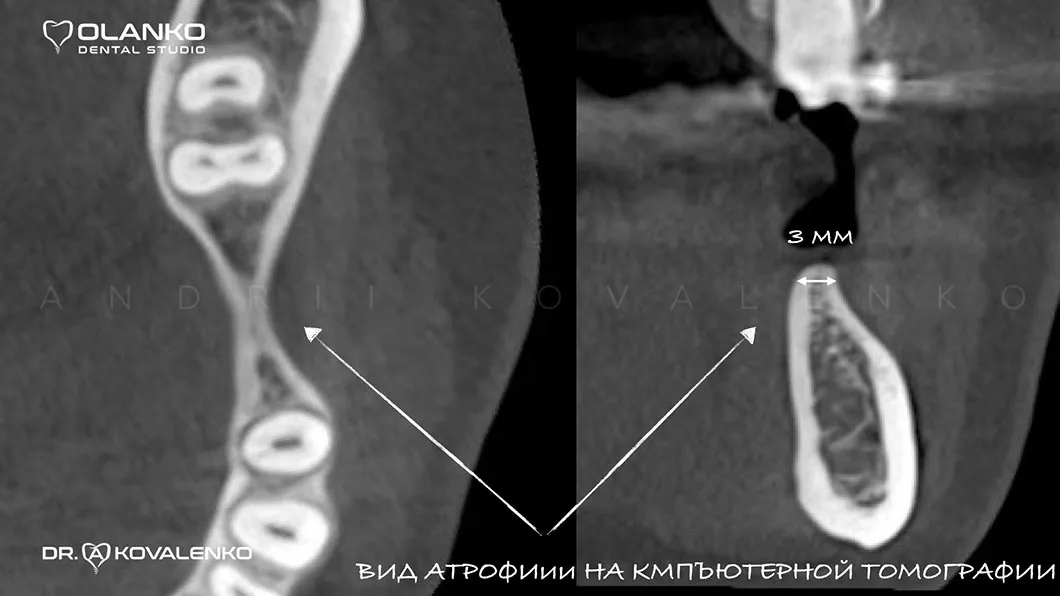

Атрофия — это прогрессирующая убыль костной ткани, которая сопровождается уменьшением ширины и высоты альвеолярного гребня. Развивается после удаления зуба и является самым распространённым препятствием для установки зубного имплантата.

Атрофия — это прогрессирующая убыль костной ткани | Оланко Бровары Киев

Специалисты Olanko dental studio (Оланко) г. Бровары, при выборе метода костной пластики, проводят детальный анализ компьютерной томографии и виртуально расставляют положение будущих имплантатов в специальном программном обеспечении IMPLANT STUDIO 3Shape.